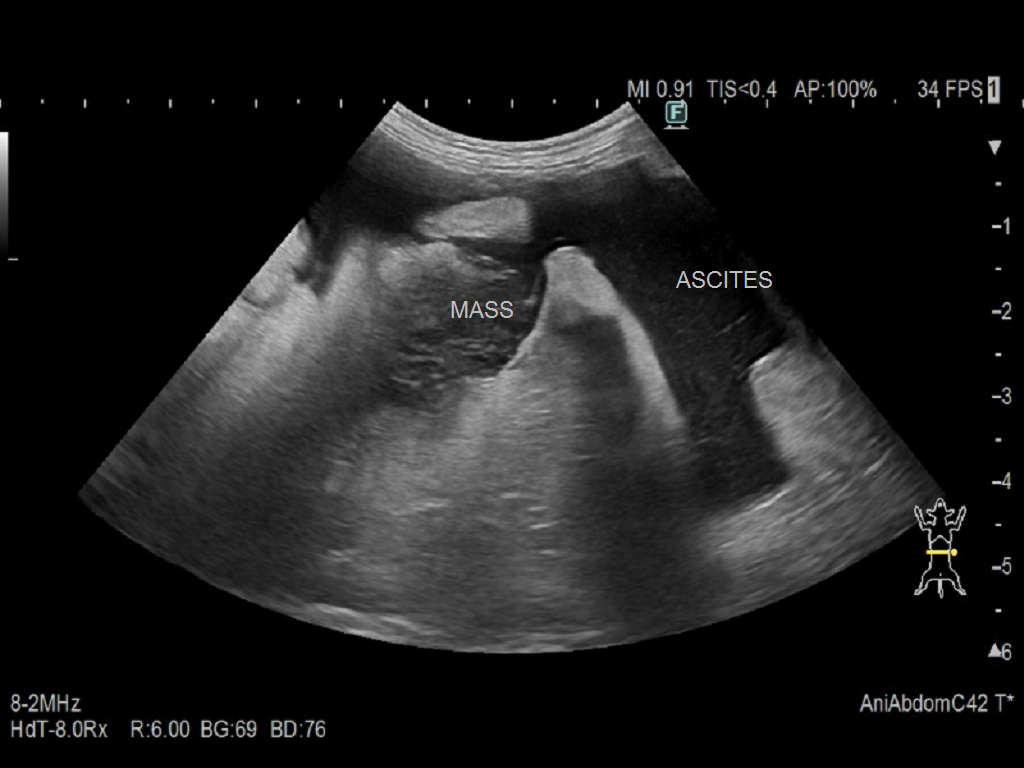

身体検査:粘膜蒼白、腹部膨満 血液検査:貧血(PCV 20%)、凝固異常(PT延長、APTT延長) 画像検査: ・X線検査:腹水の貯留が認められた。 ・腹部超音波:脾臓に多発性の低エコー性病変を認めた(図1)。多量の腹水を確認した(図2)。超音波ガイド下で腹腔穿刺を実施し、血様液を採取した。診断